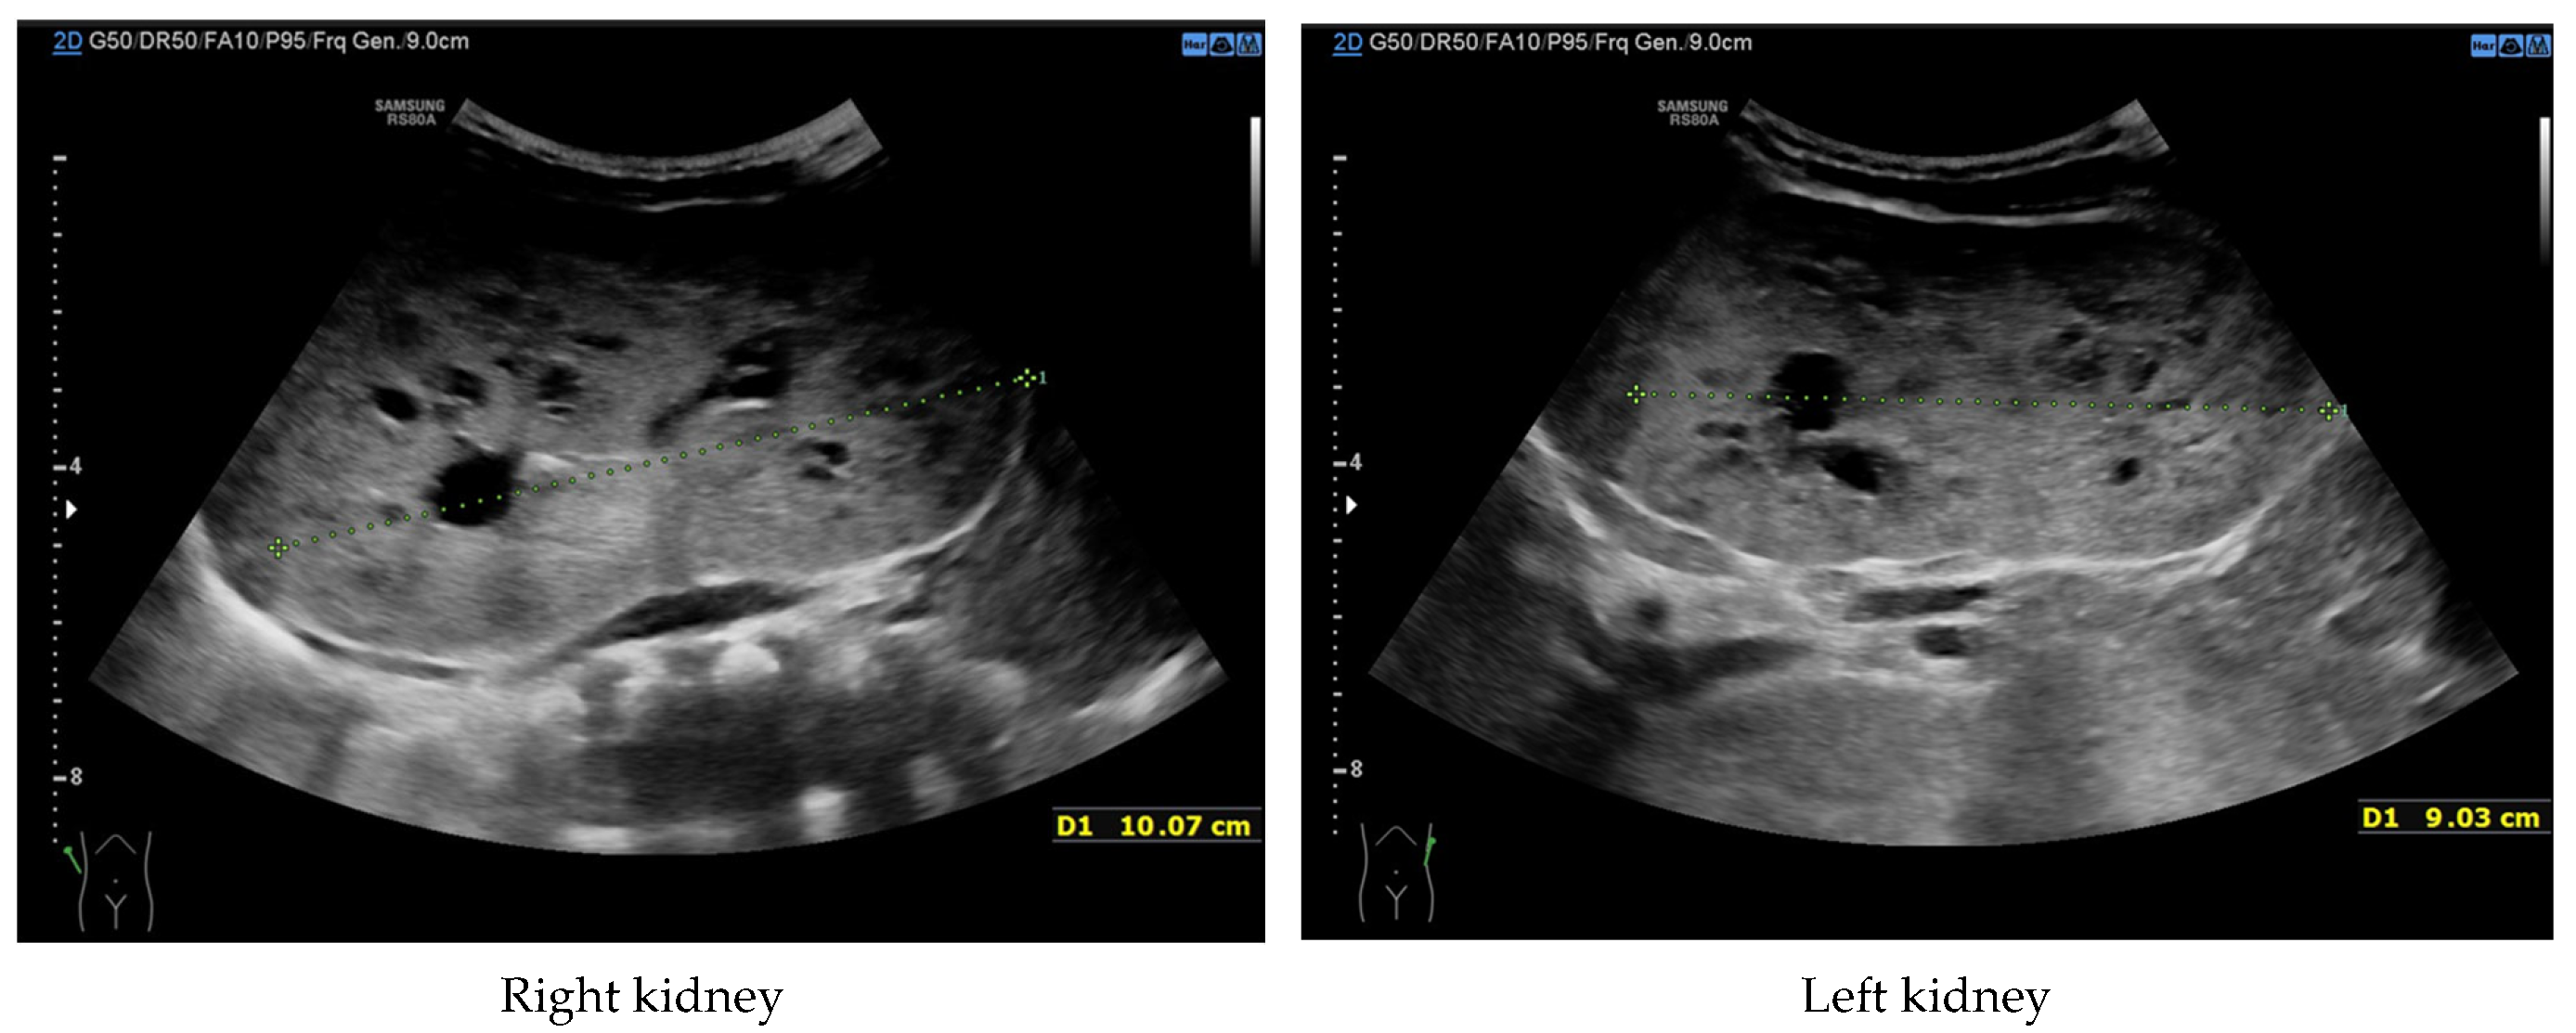

At 4 months of age, the boy was admitted to the hospital due to a hypertensive crisis (BP 162/128 mmHg). Chest X-ray demonstrated cardiomegaly, and echocardiography (ECHO) showed a significant left ventricular hypertrophy and impaired contractility. Abdominal US detected increased kidneys length (right: 101 mm (z-score 8.72); left: 90 mm (z-score 6.59)), with increased echogenicity and loss of corticomedullary differentiation, as well as numerous cysts 5–6 mm in diameter. The liver was enlarged with increased echogenicity with cysts 6–8 mm in diameter (Figure 1 and Figure 2). Doppler US demonstrated high-resistance intrarenal blood flow (RI: 0.75–0.84). Laboratory tests showed microcytic anemia, renal function was assessed as serum creatinine, the glomerular filtration rate (GFR) was estimated according to the Schwartz formula, and liver function was all normal. The boy received multi-drug therapy to control hypertension and heart failure. ECHO, performed after 6 months, was correct.

Figure 1. Ultrasonography of kidneys at the age of 4 months (enlarged kidneys with multiple cysts).